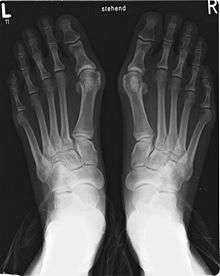

A bunion is a deformity of the joint connecting the big toe to the foot. It is characterized by medial deviation of the first metatarsal bone and lateral deviation of the hallux (big toe), often erroneously described as an enlargement of bone or tissue around the joint at the bottom of the big toe (known as the metatarsophalangeal joint).

The bump itself is partly due to the swollen bursal sac or an osseous (bony) anomaly on the metatarsophalangeal joint. The larger part of the bump is a normal part of the head of the first metatarsal bone that has tilted sideways to stick out at its distal (far) end.

Bunions are commonly associated with a deviated position of the big toe toward the second toe, and the deviation in the angle between the first and second metatarsal bones of the foot. The small sesamoid bones found beneath the first metatarsal (which help the flexor tendon bend the big toe downwards) may also become deviated over time as the first metatarsal bone drifts away from its normal position. Arthritis of the big toe joint, diminished and/or altered range of motion, and discomfort with pressure applied to the bump or with motion of the joint, may all accompany bunion development. Atop of the first metatarsal head either medially or dorso-medially, there can also arise a bursa that when inflamed (bursitis), can be the most painful aspect of the process.